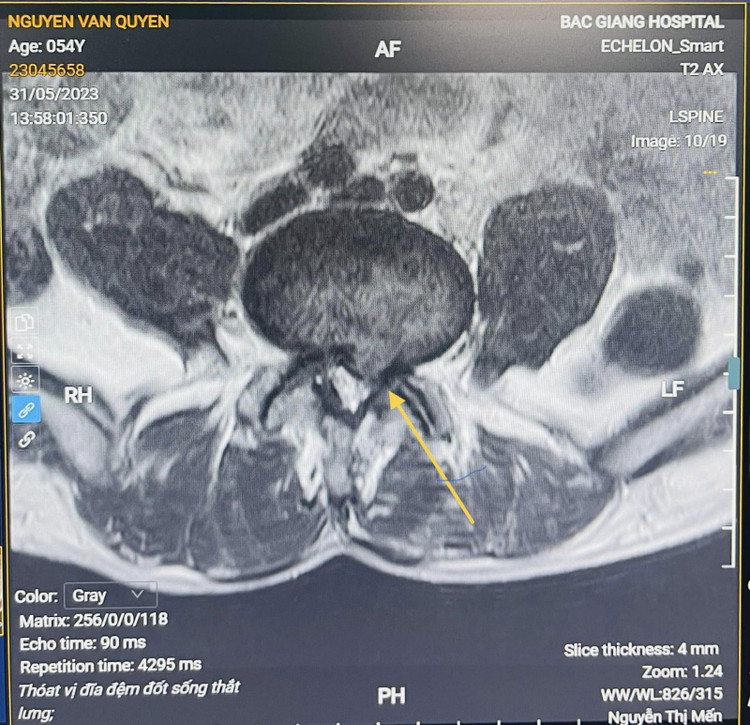

Qua thăm khám và chẩn đoán hình ảnh, bác sĩ xác định ông Q bị thoát vị đĩa đệm cột sống thắt lưng L4-L5, hẹp ống sống, hội chứng đuôi ngựa. Sau khi được bác sĩ tư vấn giải thích về phương pháp điều trị ông đã tin tưởng ở lại bệnh viện để phẫu thuật.

| Hình ảnh thoát vị trên phim chụp - ảnh BVCC |